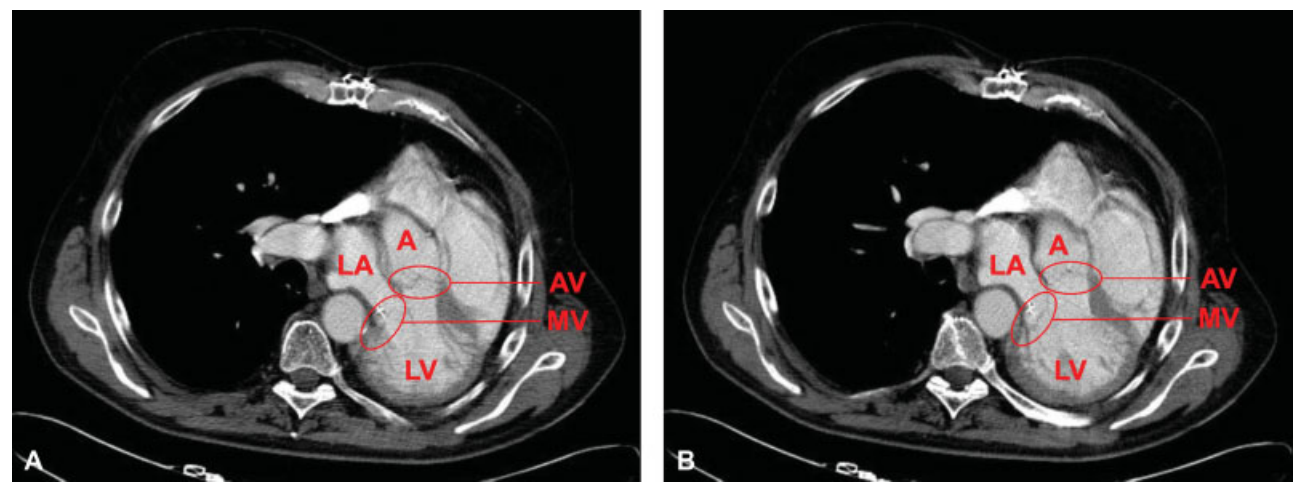

图2. 2006 年第二次二尖瓣重建手术后的胸部术前CT图。左肺切除术后,心脏在胸腔左侧内旋转移位。由于纵隔移位,胸骨正中切开术为暴露二尖瓣的最佳位置提供了可能。

肺切除术后的开胸手术属于高风险手术,因为患者会出现纵隔移位(图 2)。这就导致了异常的解剖条件,往往会使包括介入在内的手术变得困难。一般来说,边缘对边缘的MitraClip术和用于减少瓣环扩张的新策略(如 Carillion术)可用于经导管二尖瓣修复术。此外,最近还开发出了几种经导管二尖瓣置换系统(如 Tendyne术)。然而,迄今为止,还没有关于肺切除术后介入性二尖瓣重建或置换的病例。这可能是由于心脏位置的改变,使得在正确位置植入介入装置变得复杂。因此,虽然手术很困难,但结果往往更可预测。出于同样的原因,在本病例中,作者排除了介入治疗方案。

大多数心脏瓣膜手术都是在右侧肺切除术后进行的。肺切除术对心脏位置的长期影响主要表现在左侧肺切除术后心脏的旋转移位。手术策略必须考虑以下几点:纵隔明显扭曲导致的异常解剖结构,心脏向左侧完全移位导致的降主动脉对左心房的压迫,建立体外循环的插管选择,目标区域的暴露。尤其是在进行右侧肺切除术后,应考虑采用微创方法对二尖瓣进行手术。最合适的手术方法应在做完心脏CT后再进行确定。在本病例中,由于心脏旋转到左胸,胸骨正中切开术提供了完美的二尖瓣暴露。目前还不清楚降主动脉和二尖瓣之间可能存在的干扰是否导致二尖瓣环变形。这可能是二尖瓣反流复发的原因之一。